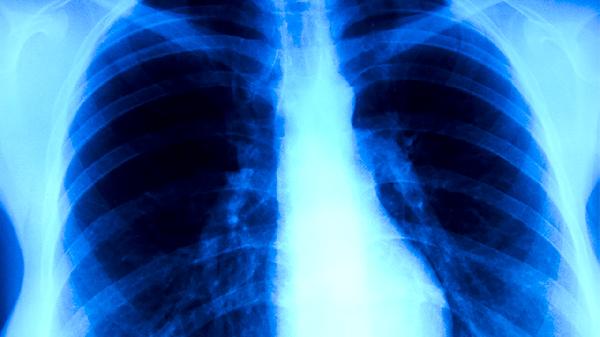

长期低流量吸氧是肺心病的基础治疗手段,适用于存在低氧血症的患者。通过鼻导管或面罩每日吸氧15小时以上,维持血氧饱和度在90%以上,可缓解呼吸困难症状,延缓肺动脉高压进展。家庭氧疗需配备制氧机,避免使用工业氧气。急性加重期需根据血气分析结果调整氧流量。